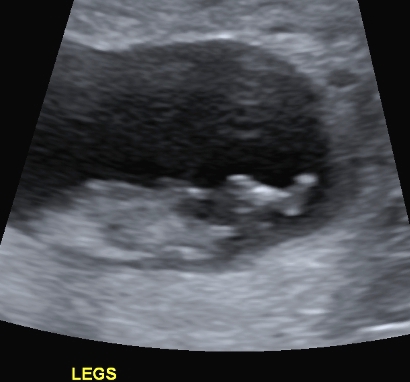

I finally managed to get hold of my u/s disc and have selected a few of the pics I think could have a nub in them (I'm still pretty hopeless at working out nubs).

There is only 1 pic from my 19 week scan that even comes remotely close to the bottom region and I'm pretty sure it is not a potty shot, just of legs from above I think??? (second last pic...biggest one)...I'm a little p'd off with the tech as I asked him to get a pic for me and he obviously didn't.

I have included quite a few from my early scan but bub was 11w4d so I understand prob slightly early still.